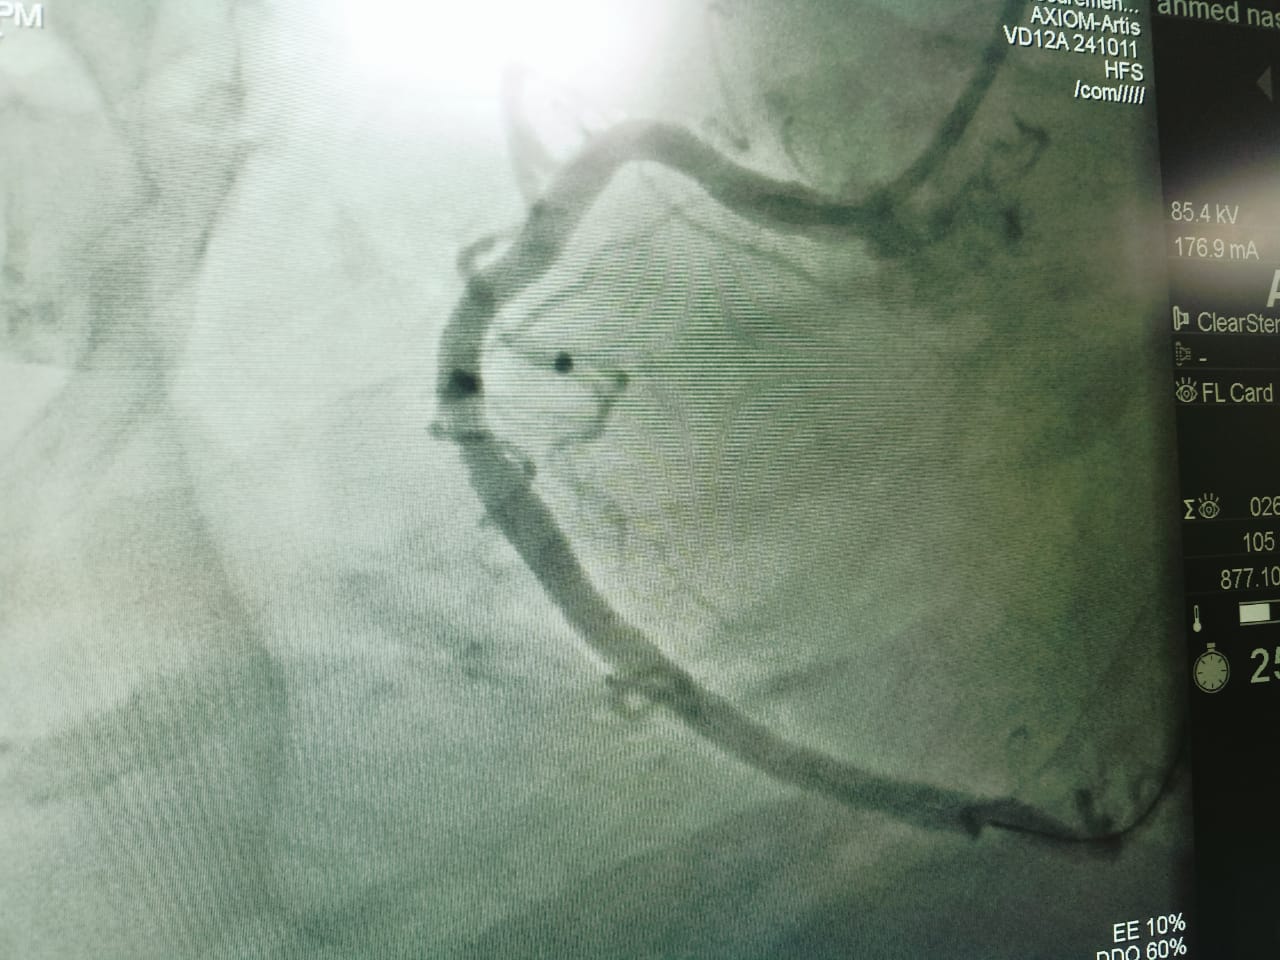

وأشار محمود عبدالفتاح مدير الإعلام والعلاقات العامة بالمديرية، إلى أن حالات القسطرة القلبية المائة التي تم إجراؤها بمستشفى فاقوس المركزي منذ تشغيل الوحدة في ٢٤ فبراير الماضي، تنوعت ما بين ٥٩ حالة قسطرة تشخيصية، و٤١ حالة قسطرة علاجية والتي تضمنت تركيب دعامات وتوسيع الشرايين باستخدام البالون، وتم خلالها إنقاذ حياة العديد من الحالات الطارئة الحرجة، وتم خروج جميع المرضى بفضل الله بحالة جيدة، بعد تقديم الرعاية الطبية اللازمة لهم قبل وبعد إجراء القسطرة القلبية بالمستشفى.